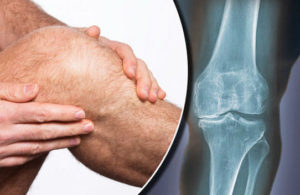

Артроз – это болезнь суставов, связанная с разрушением хрящей. Причиной недуга могут быть травмы, гормональные и обменные нарушения, пороки развития, воспаления и инфекции. Тогда как основными факторами развития являются избыточная масса тела и неполноценный рацион с дефицитом белков и микроэлементов.

Наиболее частой формой артроза коленного сустава является – гонартроз. Связано это с повышенной природной нагрузкой: так, на колени приходится вся масса тела человека, при этом давление усиливается в несколько раз при дополнительном подъеме груза.

Обычно артроз прогрессирует постепенно: появляются «стартовые» боли в колене, скованность по утрам, а также снижение объема движений. Итогом болезни зачастую является инвалидность, из-за чего недуг требует не только лечения, но и модификации образа жизни: отказа от вредных привычек и следования специальной диете при артрозе коленного сустава.